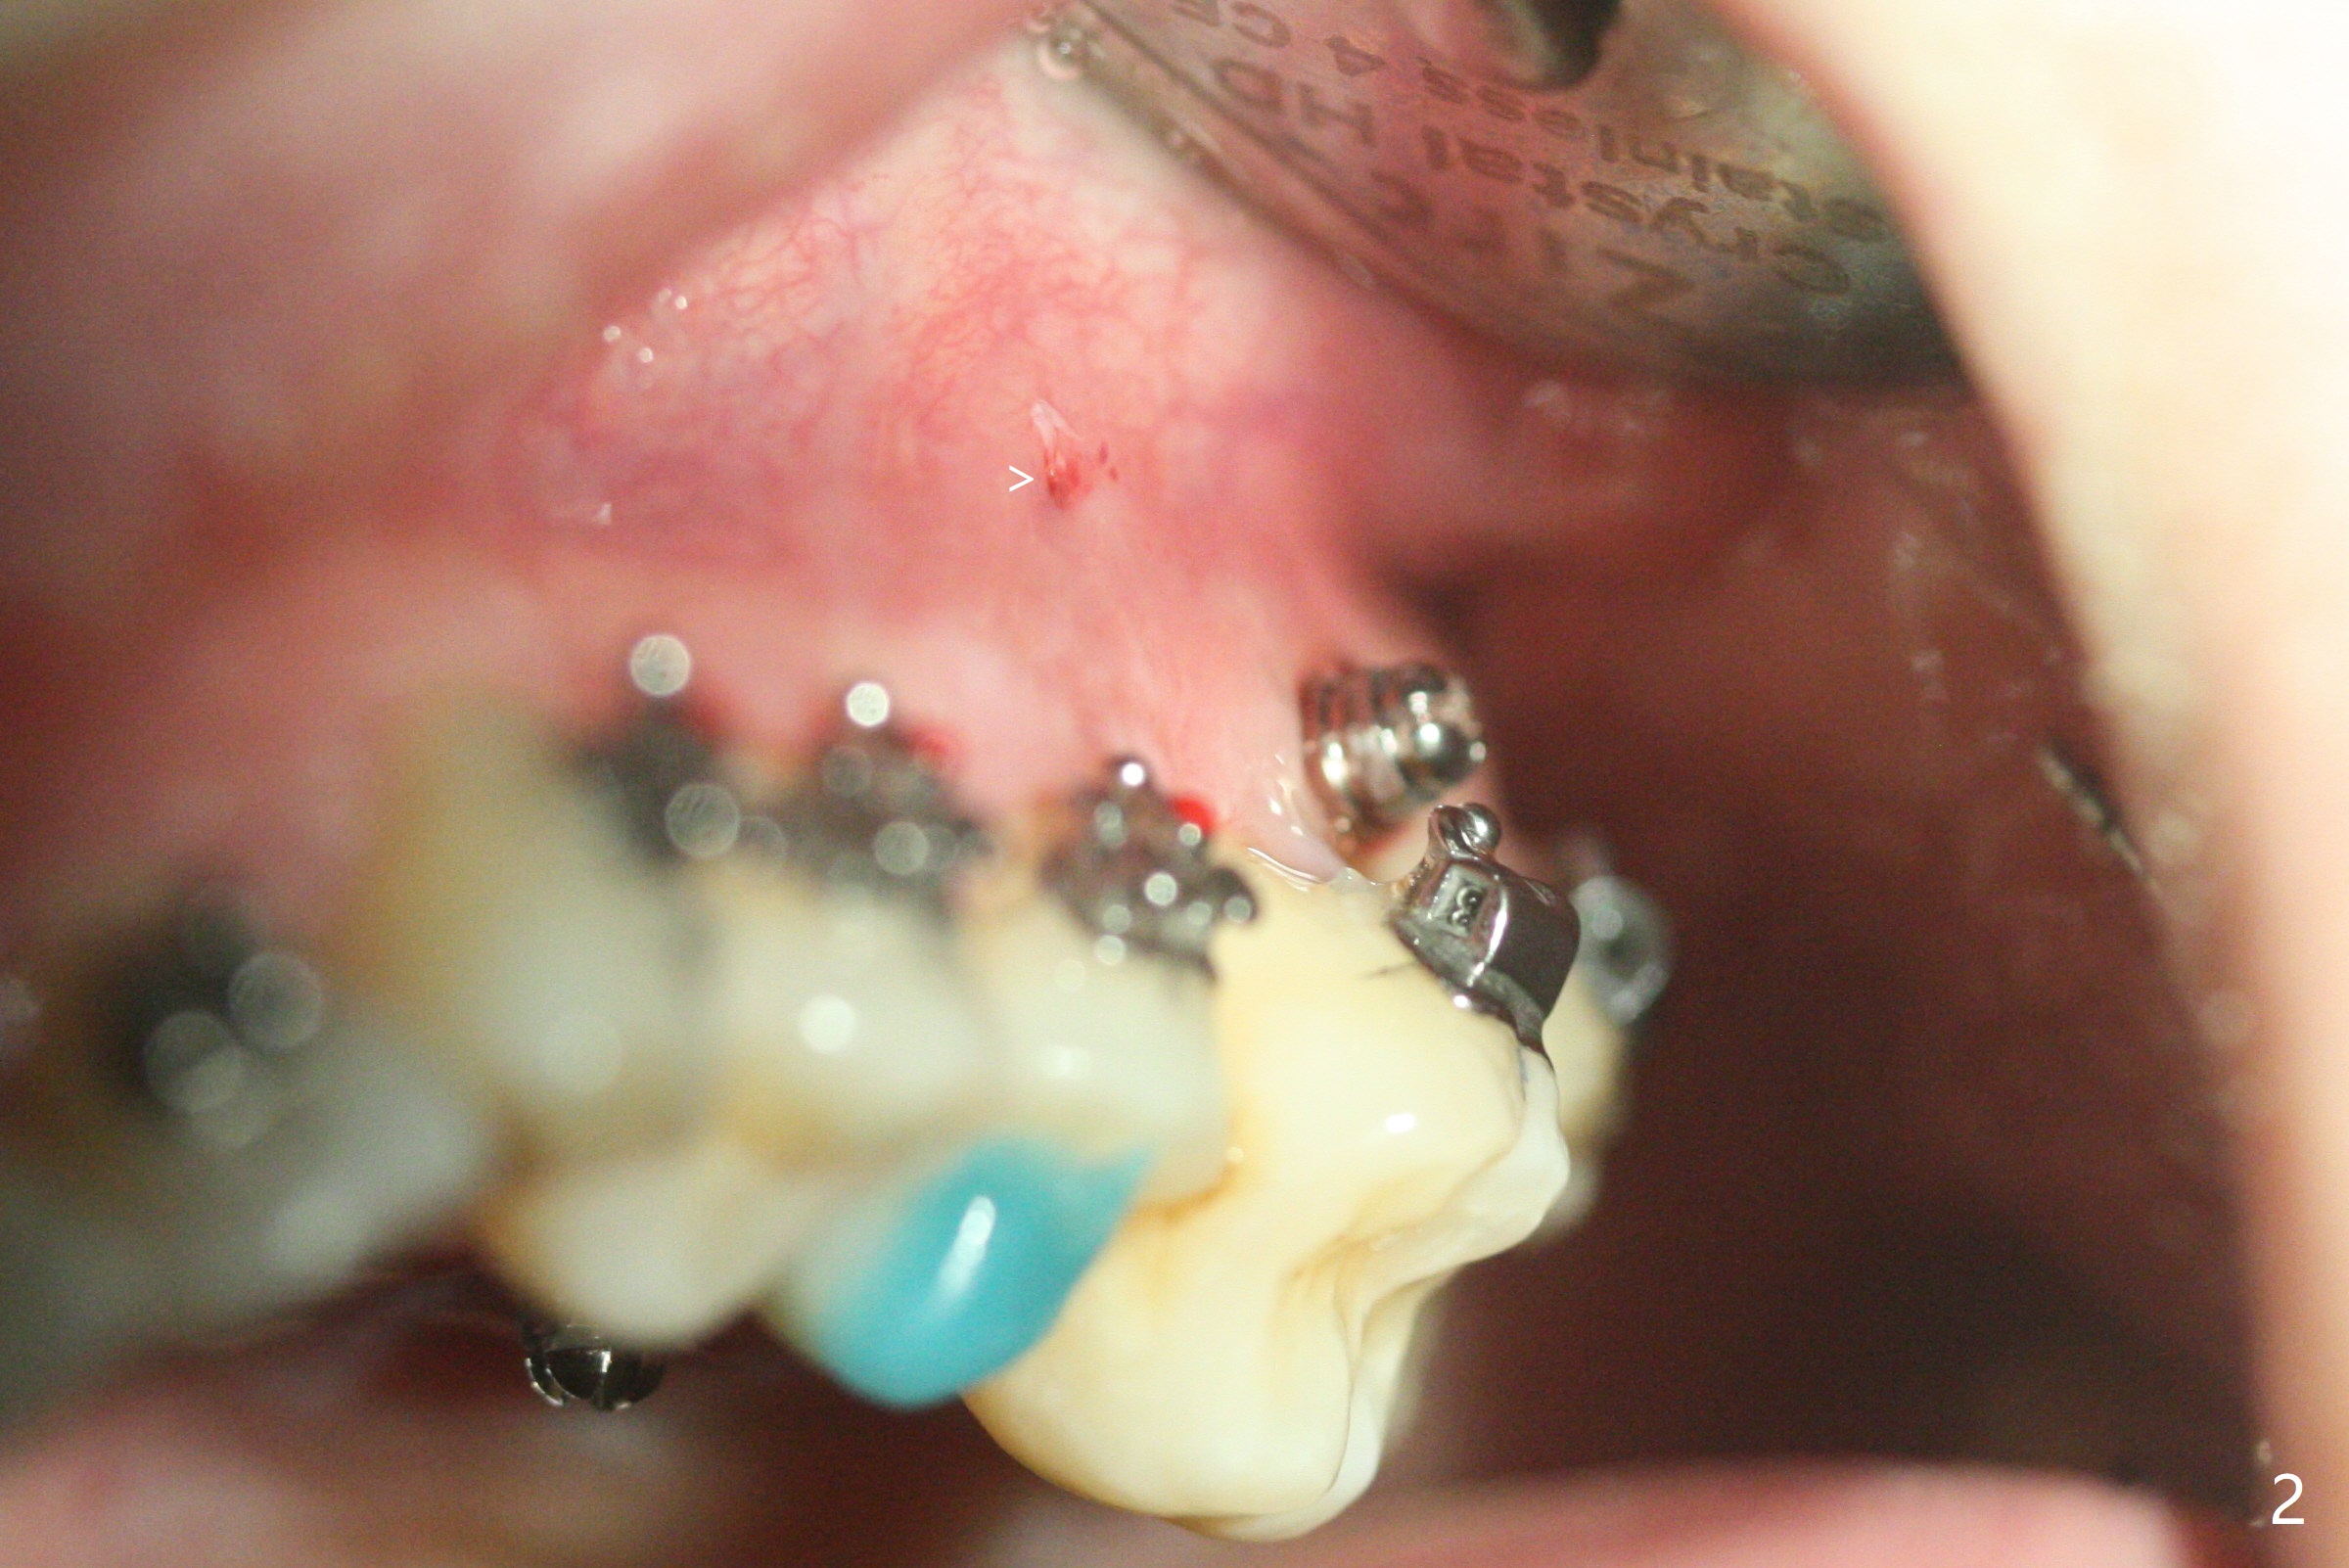

矫正器放置后一个月,正好有充裕时间,匆忙研究全景片(最好CT),好像左上6近中间隙大,近中颊侧,远中腭侧似乎是种植位点(图一:白圆圈),植入越高越宽,不容易伤及邻牙牙根。但是微型植体种植原则是必须种植在角化龈,减少炎症(以前不明白为什么)。当植体在移动牙龈植入时(图二:白箭头),牙龈浮起来,估计非角化牙龈也不能与植体产生紧密结合。取出后,完全可以在6近中颊侧角化龈植入,但是仔细检查发现远中颊侧角化龈更宽,所以在那里扎根(图二:黑箭头),因此腭侧就得选择近中(图三)。微型植体可以即刻使用,power chains常滑脱,压迫牙龈,在这个病例很可能进入远中牙间隙,所以需要在远中边缘嵴加树脂(图四,五:* (1.6x8mm))。第二天远中颊侧植体松动,取出后,插入2x10毫米一段式植体,仍然松动(图六)。CT显示植体下缘穿破牙槽骨(图七,骨质吸收严重与图八近中牙槽骨高度对比)。如果在近中颊侧重新植入微型植体,必须使用6毫米长植体(图九),所以最好在远中颊侧重新植入(图十:红色),缺损区(黑色)植骨。在使用14 niti时,左下7松动,病人同意拔除8,以后后推7,然后6种植(图十一:(左上8已拔除(x))),同时左上6远中植骨,左下8远中牙槽窝放置浸泡PRF液体胶原塞(图十二:1),近中牙槽窝粘性骨粉(2),最后牙槽窝上部PRF膜(3),PGA缝线。可能需要Cytoplast。